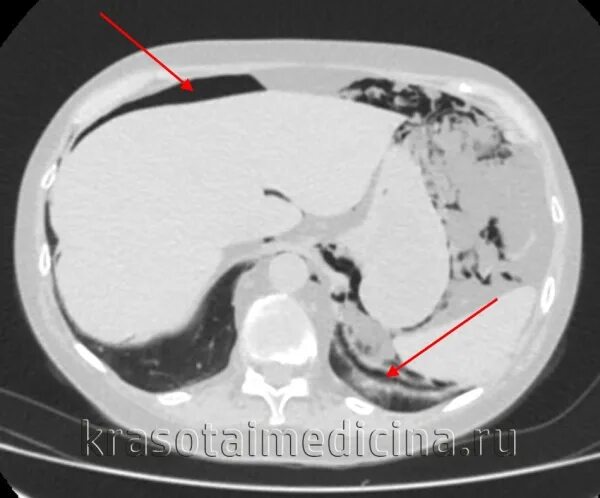

Язва желудка кт